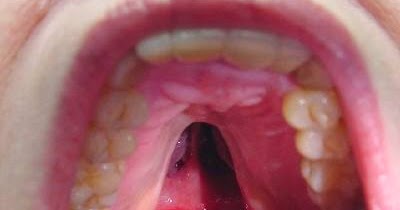

Dr Khaled Auf Twitter التخدير في سقف الفم أكثر تخدير يسبب آلم للمريض كون هذه المنطقة شفافة جدا Thin Mucosa لذلك ينصح لن تكون كمية التخدير لا تتجاوز 1 3mm يعني مجرد قطرات قليلة

أستاذ تجميل فتحة سقف الحلق من أهم العيوب الخلقية عند حديثي الولادة

علاج الشفة المشقوقة وشق سقف الحلق

علاج شق سقف الحلق بأفضل الطرق 2020 دكتور صابر عبد المقصود